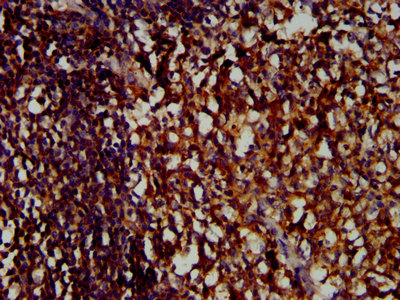

IHC image of CSB-PA847747LA01HU diluted at 1:400 and staining in paraffin-embedded human tonsil tissue performed on a Leica BondTM system. After dewaxing and hydration, antigen retrieval was mediated by high pressure in a citrate buffer (pH 6.0). Section was blocked with 10% normal goat serum 30min at RT. Then primary antibody (1% BSA) was incubated at 4°C overnight. The primary is detected by a biotinylated secondary antibody and visualized using an HRP conjugated SP system.